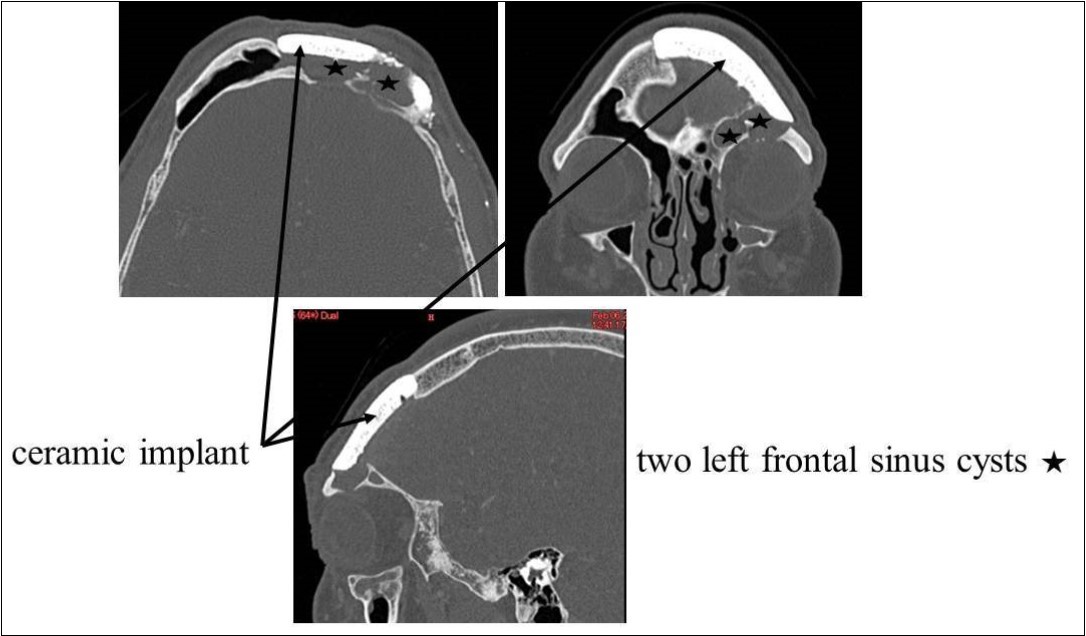

Recurrent frontal sinusitis was suspected, and the patient was referred to our department for evaluation on February 14, 2007. On initial evaluation, the left upper eyelid swelling was resolved; however, paranasal sinus computed tomography (CT) showed two left frontal sinus cysts (Figure 1). The patient had a history of hypertension that was well-controlled on oral medications. No other major disorders were present, including diabetes or heart disease.

Figure 1.CT of the paranasal sinuses showed two left frontal sinus cysts. Black arrows: ceramic implant. Black stars: two left frontal sinus cysts